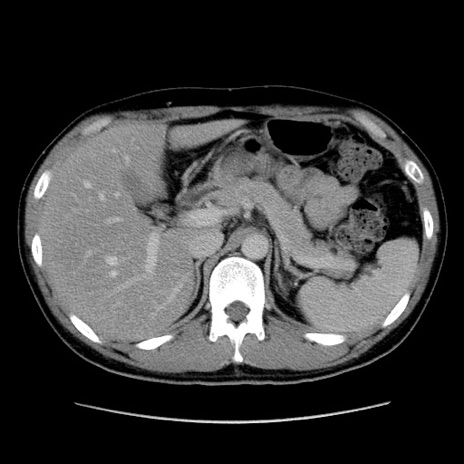

冠状断像

【症例】20歳代 男性

【主訴】心窩部痛

【現病歴】今朝より上腹部痛あり。一旦軽快していたが再度出現したため救急要請。昨日夕に白身の魚を含む刺身を食べた。

【身体所見】BP 136/89mmHg、HR 74/min、BT 37.0℃、腹部:膨満、軟、心窩部に圧痛あり。反跳痛なし、筋性防御なし、腸雑音やや亢進あり。

【データ】WBC 17700、CRP 0.48